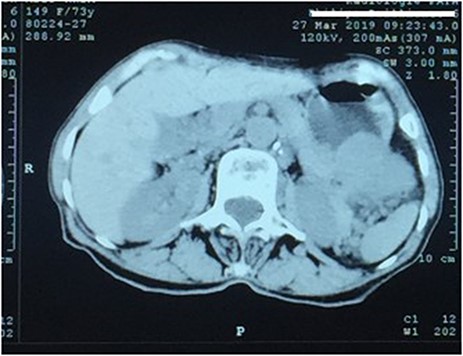

A 73-year-old woman was referred to our general surgery service. Her complain was intermittent gastric discomfort. There was no significant past medical history. There was no history of upper gastrointestinal bleed, or past surgical interventions with no abnormalities found on physical exam. An esophagogastroduodenoscopy (EGD) revealed a submucosal mass in the gastric body. Biopsy of the mass showed no evidence of malignancy. Computerized tomography (CT) scan of the abdomen showed an exophytic solid homogeneous mass along the greater curvature of the stomach and partly projected into the gastric lumen, causing smooth indentation measuring 8 × 8 × 6 cm3 (Fig. 1). The patient’s laboratory results were unremarkable. A presumptive diagnosis of GIST was made. The patient underwent successful wedge resection of the mass through laparotomy and the specimen was sent to pathology. On gross examination, a white intramural, nodular, solid mass measuring 8.7 × 8.8 × 6.7 cm was seen. A cut section revealed whirling trabeculation with a biphasic proliferation of compact hypercellular areas and myxoid hypocellular areas (Fig. 2). Sections from the tumor showed interlacing bundles of spindle cells, which had elongated nuclei, ill-defined cytoplasmic borders and palisading nuclei (Fig. 3). No nuclear atypia was noted. No mitotic activity and no necrosis were identified. There was no lymph node involvement and the surgical margin was negative for tumor cells. A histological diagnosis of a benign mesenchymal tumor was made. Immunohistochemistry (IHC) staining was strongly positive for S-100 (Fig. 4), whereas c-Kit, CD 34; DOG 1; smooth muscle actin (SMA), desmin and AE 1/AE 3 were negative. Hence, a final diagnosis of schwannoma was made. The postoperative period was uneventful and the patient was dismissed from the hospital after 5 days.

CT scan showing an exophytic mass in the great curvature of stomach wall

CT is widely used in clinical examinations. GS usually shows a well-defined, oval, submucosal tumor in the stomach with an exophytic or mixed growth pattern and moderate homogeneous enhancement like the case was in our patient as well. GS frequently co-occurs with swelling perigastric lymph nodes [7].